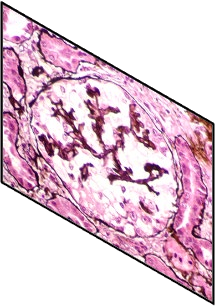

With the rapid development of self-supervised learning (e.g., contrastive learning), the importance of having large-scale images (even without annotations) for training a more generalizable AI model has been widely recognized in medical image analysis. However, collecting large-scale task-specific unannotated data at scale can be challenging for individual labs. Existing online resources, such as digital books, publications, and search engines, provide a new resource for obtaining large-scale images. However, published images in healthcare (e.g., radiology and pathology) consist of a considerable amount of compound figures with subplots. In order to extract and separate compound figures into usable individual images for downstream learning, we propose a simple compound figure separation (SimCFS) framework without using the traditionally required detection bounding box annotations, with a new loss function and a hard case simulation. Our technical contribution is four-fold: (1) we introduce a simulation-based training framework that minimizes the need for resource extensive bounding box annotations; (2) we propose a new side loss that is optimized for compound figure separation; (3) we propose an intra-class image augmentation method to simulate hard cases; and (4) to the best of our knowledge, this is the first study that evaluates the efficacy of leveraging self-supervised learning with compound image separation. From the results, the proposed SimCFS achieved state-of-the-art performance on the ImageCLEF 2016 Compound Figure Separation Database. The pretrained self-supervised learning model using large-scale mined figures improved the accuracy of downstream image classification tasks with a contrastive learning algorithm. The source code of SimCFS is made publicly available at https://github.com/hrlblab/ImageSeperation.